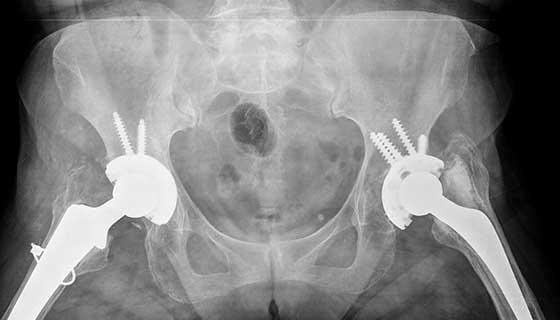

Situated in the heart of Delhi, Delhi Orthopaedic Clinic offers unparalleled orthopaedic and joint services to the general population. Right from appointment to consultation and beyond DOC strives for personalized care with an emphasis on accurate assessment and ethical advice. The vision of DOC is to provide focused comprehensive and personalized care to orthopaedic patients esp. knee and hip joint replacement.